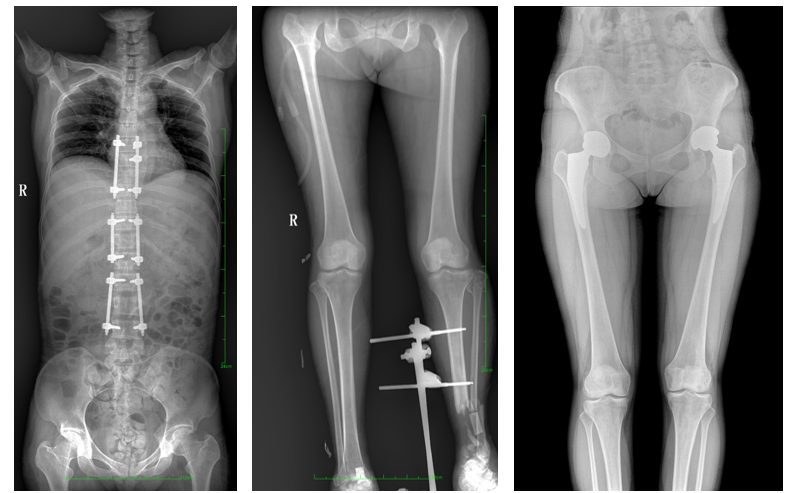

17"*34"有效視野,是市面大尺寸平板的2倍,一次成像不拼接。相較于多張攝影再軟件拼接的DR設(shè)備,PLX8600解決了拼接圖像存在密度不均勻,拼接處圖像配準(zhǔn)和放大效應(yīng)等問題,給臨床帶來了真正的大視野影像解決方案,高清畫質(zhì),準(zhǔn)確成像不失真,可一次性覆蓋全脊柱或雙下肢影像。PLX8600大視野平板動(dòng)態(tài)DR攝影速度快,患者可以更快的完成檢查,且單次攝影輻射劑量是常規(guī)多張攝影再軟件拼接DR的1/2或1/3,低劑量給患者更多關(guān)愛。

除常規(guī)靜態(tài)攝影外,PLX8600大平板具備動(dòng)態(tài)透視和點(diǎn)片功能,透視采集功能可支持大視野、多角度的可視化觀察。通過可視化的動(dòng)態(tài)影像,配合點(diǎn)片功能,能夠很好的觀察復(fù)雜部位病灶,有效的抓取關(guān)鍵幀,降低患者多次攝片的概率,安全又高效。如:全脊柱狀態(tài)評(píng)估、長骨關(guān)節(jié)活動(dòng)度、下肢靜脈造影瓣膜功能評(píng)估、消化道功能評(píng)估、脊髓造影等更多大視野臨床應(yīng)用,多面手給醫(yī)生更多驚喜。